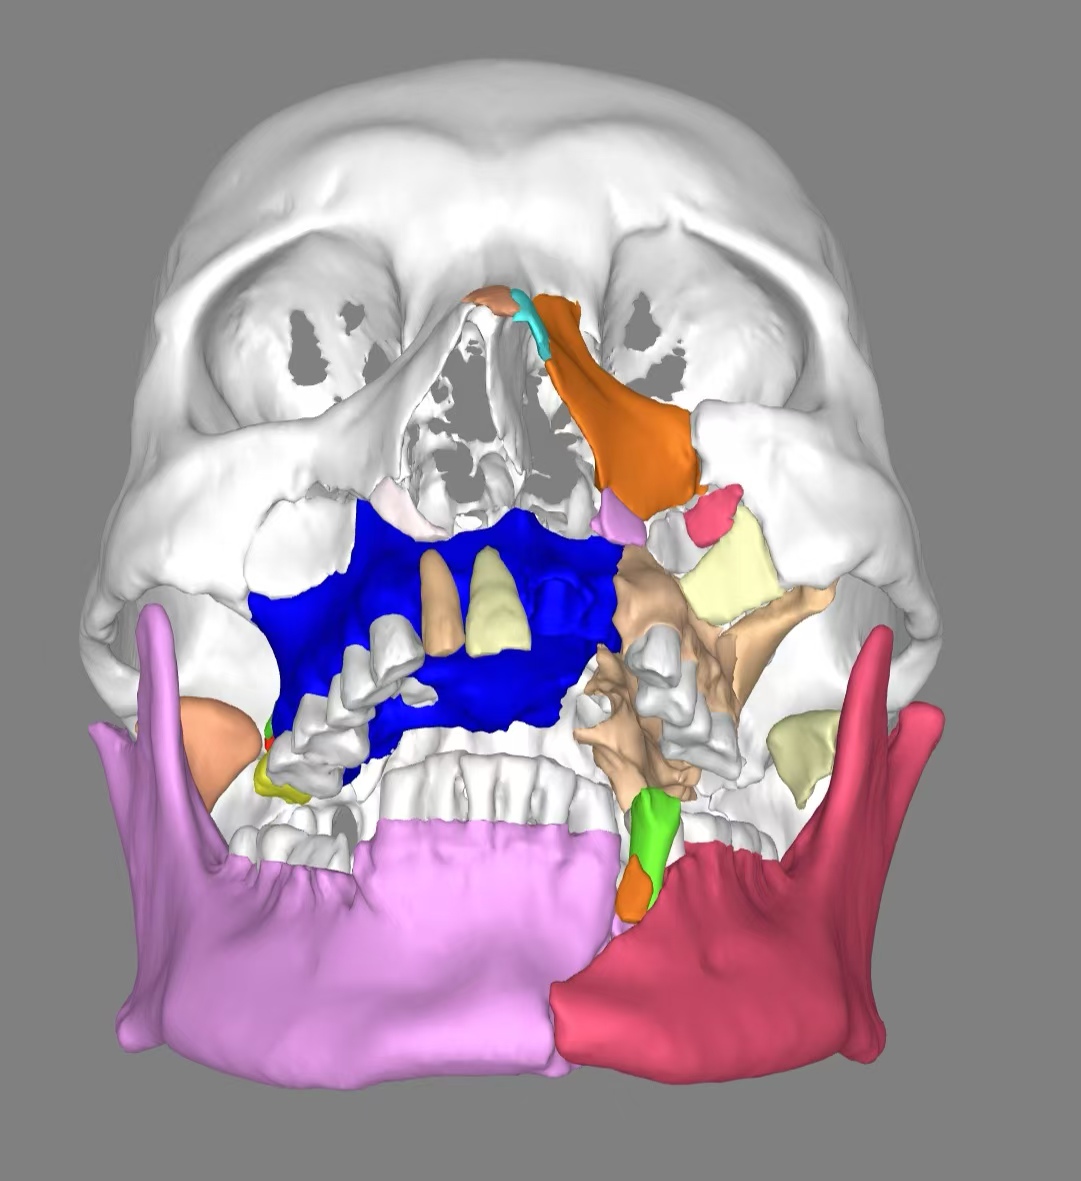

姬先生入院后,我院整形外科(颌面骨科)主任胡沛、副主任医师马莉及主治医师田振江诊疗团队高度重视,面对这种高难度手术,科室组织大家进行病情讨论并进行全面评估,精心制定了个体化手术治疗方案。考虑到传统手术方式在面对如此复杂的颌面骨折时难度极大,团队决定借助我院先进的3D打印技术制作,成功打印出了高精度的面颅部创伤模型并进行术前设计及术中辅助复位。

借助该模型,让团队能够在术前精准模拟手术过程,详细规划骨折复位路径和内固定方案、提前进行内固定物的预制,大大提高了手术的精准性与安全性。在充分准备后,团队在主任医师胡沛与副主任医师马莉共同带领下为姬先生成功实施了陈旧性双侧上颌骨骨折切开复位内固定术、陈旧性创伤性腭裂、陈旧性双侧髁状突骨折切开复位内固定术、陈旧性下颌骨骨折切开复位内固定术,同时还利用患者的骨折部位,纠正了患者受伤前的上颌前突、开??畸形。历经八小时,手术过程顺利,术后姬先生恢复状况良好。

术前